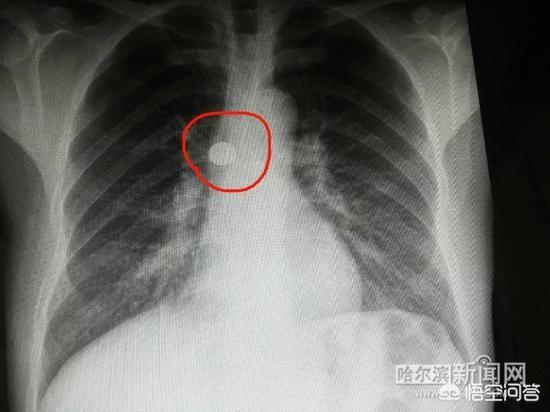

陈先生吓了一跳连夜赶到哈医大二院,经过X光胸透,确定右主支气管有圆形金属异物。由于右下肺出现感染,气管有脓性分泌物,必须尽早取出金属物,避免感染加重!